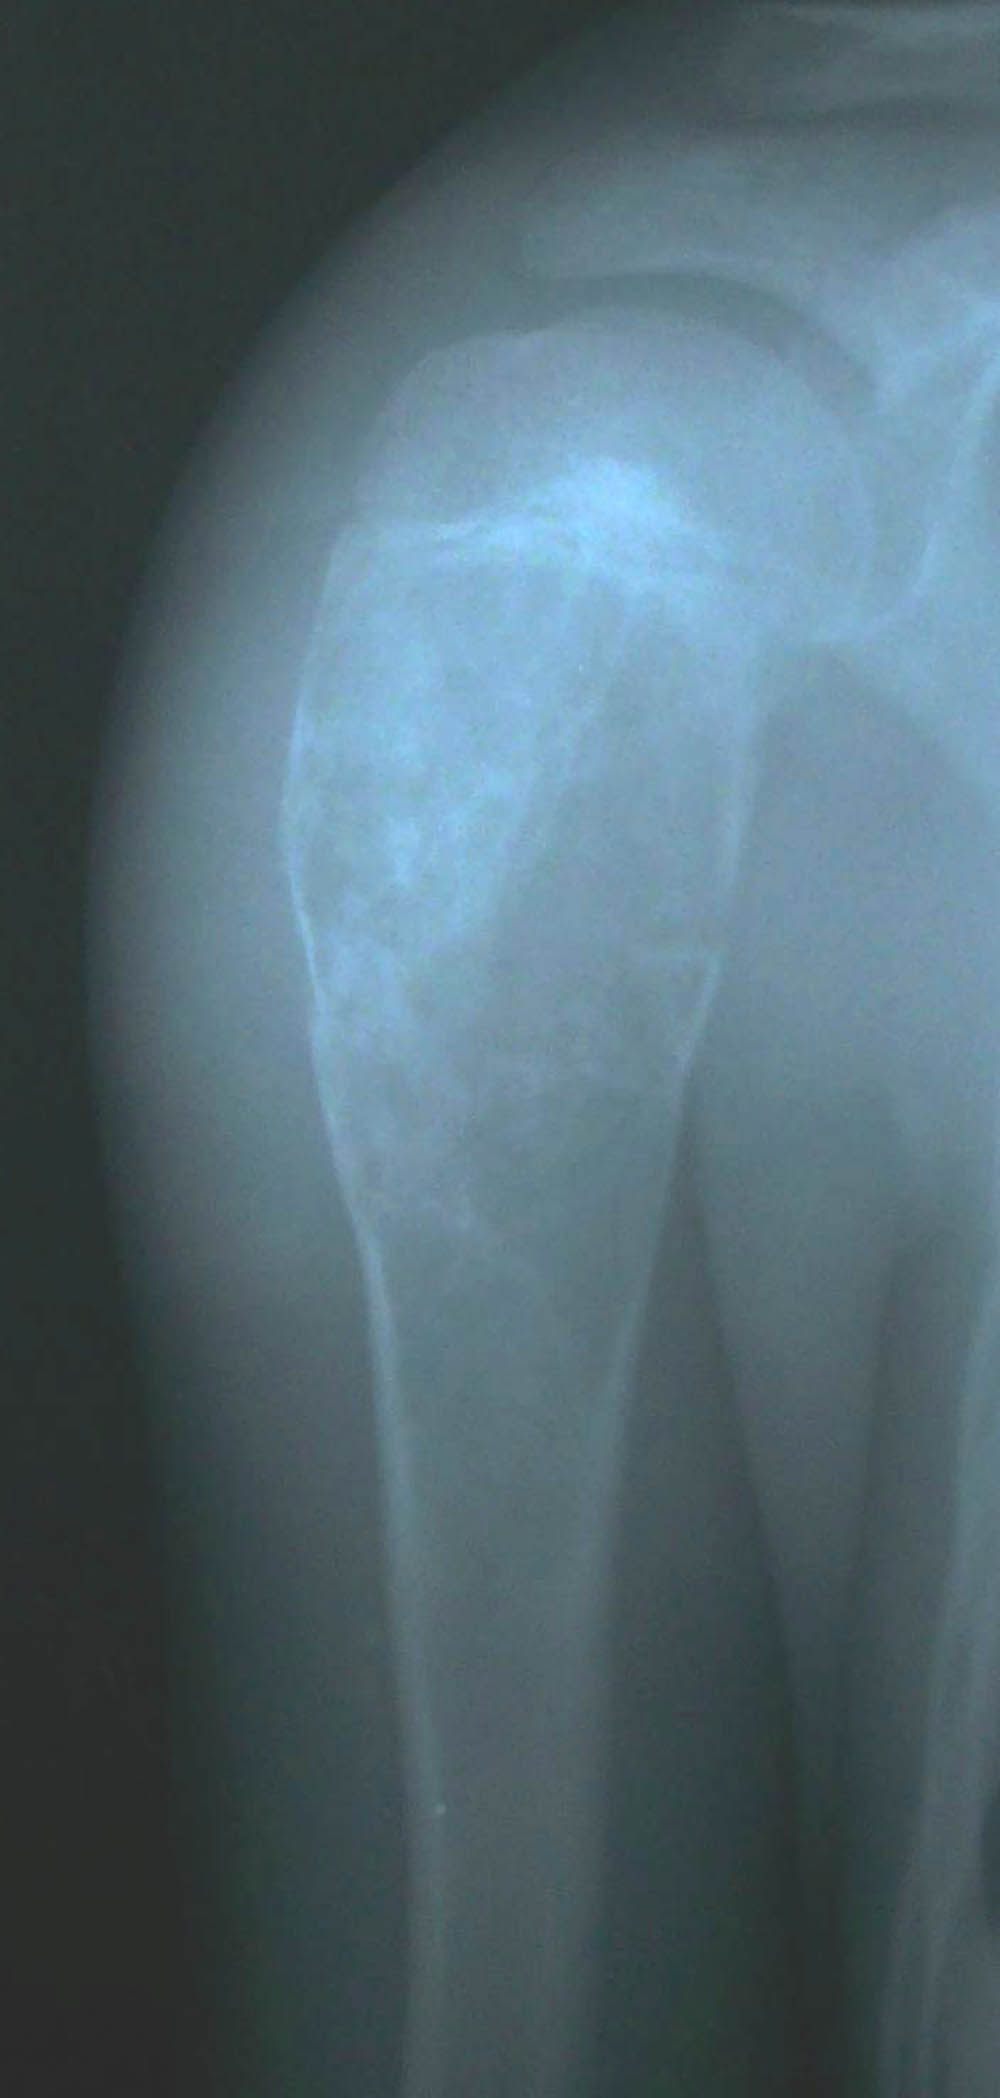

标题: X5828:骨囊肿

一小时前肩关节受外伤,一年前有外伤史

肱骨近端骨质呈多房囊状膨胀性改变,与骨干长轴方向一致,未突破骺软骨板,边缘见硬化,骨壳欠完整,可见“骨折片陷落征”,内见多个残留长短不一骨棘,软组织影无肿胀。

鉴别诊断:1、骨囊肿,典型发病年龄及部位,可见病理性骨折,较支持,不支持点是骨质膨胀较明显;

2、骨纤维异常增殖症:单骨多囊状破坏,外缘光滑,内缘毛糙波浪状,囊内外条索状骨纹及斑片状致密影具有特征性;

3、软骨母细胞瘤:骨骺部位偏心性病变,可跨越骺板;

4、abc,未突破骺软骨板,骨质膨胀;

5、软骨母合并abc。

考虑:骨囊肿合并病理性骨折可能性大,需排除骨纤、软骨母合并abc等。